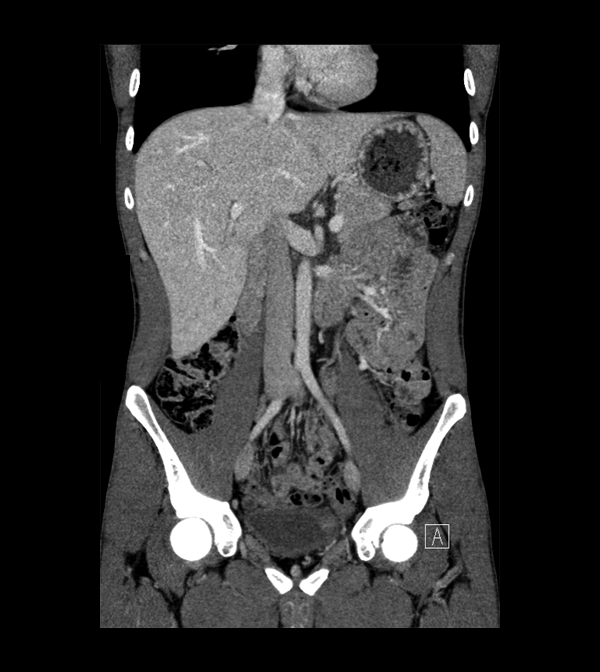

Body

Covers abdominal CT anatomy.